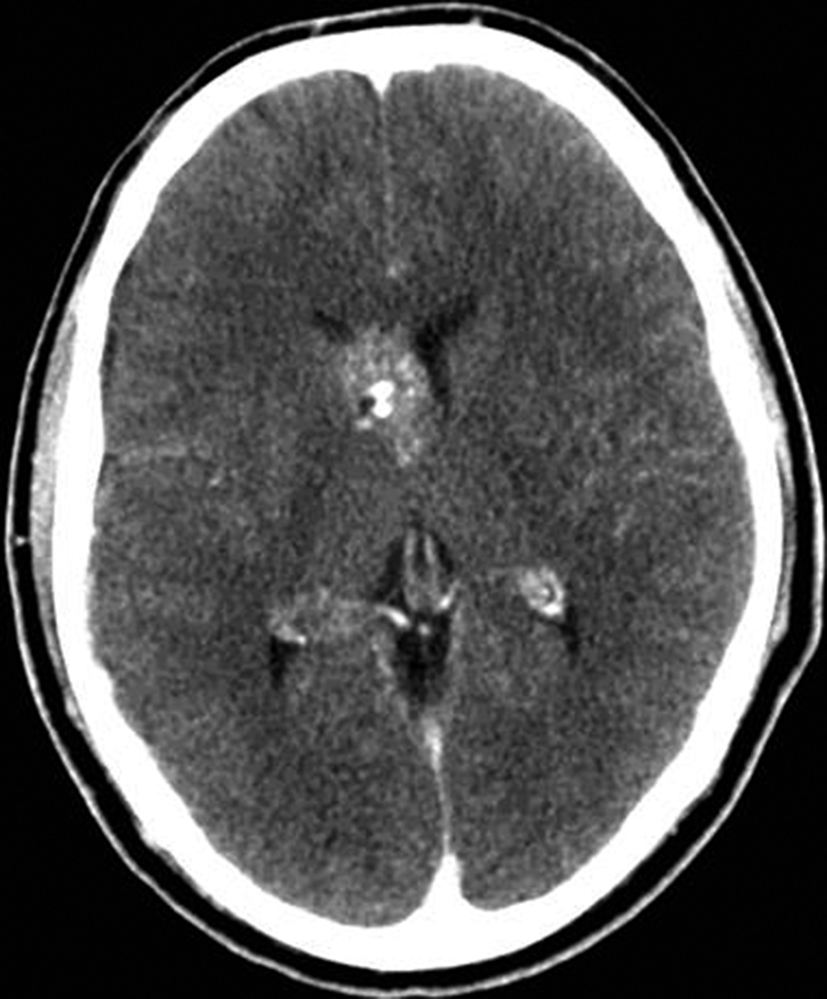

Se presenta el caso clínico de un paciente de sexo masculino, de 36 años de edad, sin antecedentes personales a destacar. Consulta por cefalea holocraneana de larga data, sin déficit neurológico y examen físico normal. Dada la clínica del paciente se realiza una tomografía computada de cráneo sin contraste intravenoso que identifica una lesión bien definida espontáneamente hiperdensa, heterogénea con calcificaciones puntiformes localizada en el asta frontal del ventrículo lateral derecho. No hay edema peri-lesional, efecto de masa ni hidrocefalia (Figura 1- A). Debido a los hallazgos se decide administrar contraste intravenoso, no evidenciándose realce significativo de la lesión (Figura 1- B).

a) TC sin contraste. Lesión intraventricular hiperdensa, heterogénea con pequeñas calcificaciones.

a) TC con contraste. No se identifica realce significativo de la lesión.

Figura 5

a y b) Cortes axiales de TC sin y con contraste intravenoso. Control tomográfico al año del estudio inicial, no se observan cambios significativos de la lesión.